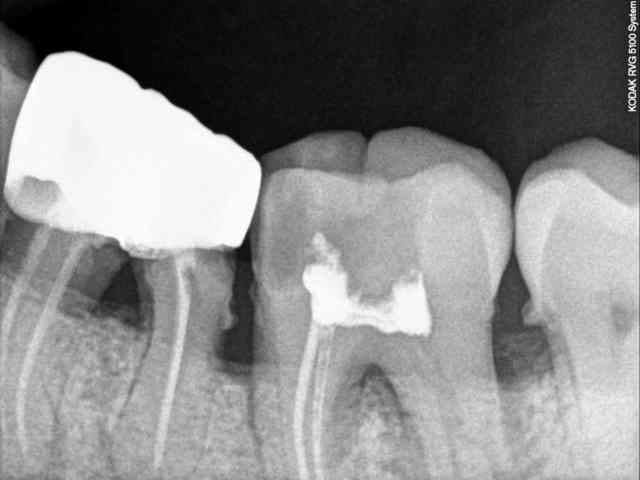

Par contre en deux urgences ce matin, j'ai une 37 avec une fracture en siflet de 7 mm en infra osseux de la racine distale

Et un jeune de 37 ans avec une valve cardiaque mecanique et une jolies 41 qui attend de faire son effet et qui me pose de gros problemes de confraternité car il vient pour autre chose.

Deux urgences sur une matinées de travail